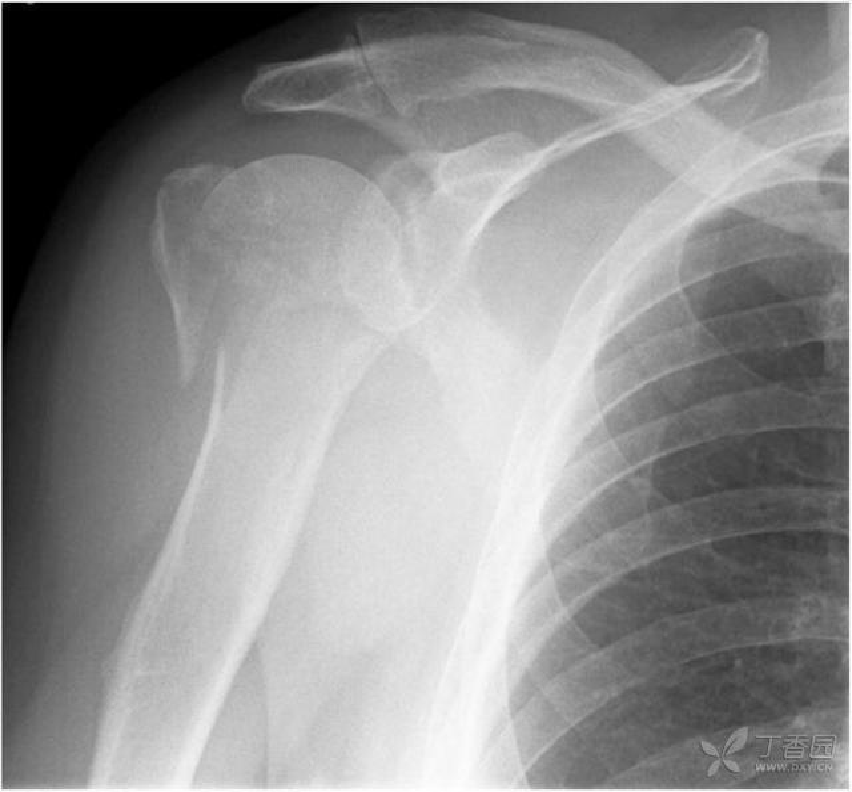

一例外展崁插四部分骨折的前后位片:

器械辅助下复位骨折,经皮穿针内固定术的最终效果